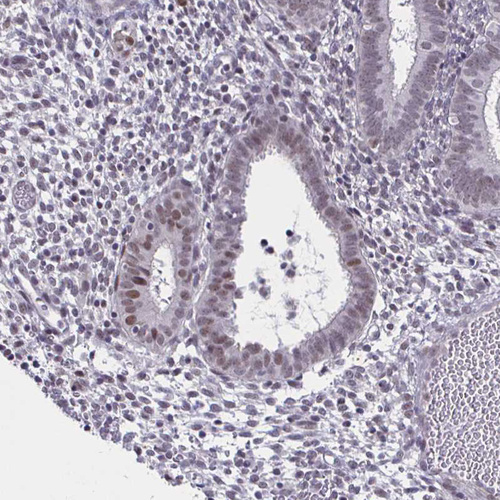

Immunohistochemical staining of human tonsil shows strong nuclear positivity in germinal center cells.